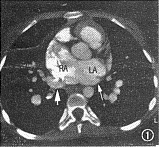

图1~6 为同一病例,部分型肺静脉异位连接(心脏型)。图1示右上肺静脉(短箭头)引流入右心房(RA),左上肺静脉(长箭头)引流入左心房(LA),房间隔缺损巨大。图2示两下肺静脉(箭头)分别引流入左右心房。RV:右心室;LV左心室。图3示下腔静脉肝段缺如:肝脏水平未见下腔静脉显影,半奇静脉粗大(箭头)。图4为表面阴影显示法三维重建,示右侧上下肺静脉(白箭头)均引流入右心房,左侧上下肺静脉(黑箭头)均引流入左心房。SVC:上腔静脉。图5为导管自下腔静脉经奇静脉入右心房经右心室至右肺动脉造影:右肺静脉(黑箭头)引流入右心房(白箭头)。图6为左肺动脉造影,示左肺静脉(白箭头)引流入左心房(白三角箭头),对比剂经房间隔缺损(黑箭头)分流入右心房

2例手术患者,完全型及部分型肺静脉异位连接各有1例。其中部分型肺静脉异位连接者EBCT显示右侧肺静脉引流入右心房,而左侧肺静脉正常回流入左心房,伴有II孔型房间隔缺损、肺动脉高压、下腔静脉肝段缺如。术前心血管造影检查及手术所见均与EBCT相同(图1~6)。1例完全型肺静脉异位连接,术前造影示单发右位心、右室双出口、肺动脉瓣及瓣下狭窄、房室间隔缺损、双上腔静脉,但心室造影未能明确肺静脉引流位置,遂行EBCT检查。EBCT除显示上述畸形外,尚显示右位主动脉弓及完全型肺静脉异位连接。